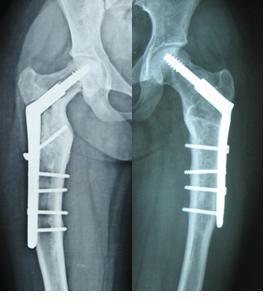

对于严重髋内翻畸形颈干角<60°,且股骨头下方有骨赘形成(如图1),肢体短缩严重者:如果继续使用DHS钢板,力求使颈干角恢复到120°时,此时髋关节头臼咬合已不匹配,臀中肌张力会更大,甚至肢体延长过多会引起坐骨神经症状。对这类患者我们采用DCS钢板,缩减颈干角为95-105°,术后患者髋关节头臼咬合基本匹配,臀中肌经轻度松解也可适应,同时也减少了坐骨神经损伤的风险。26例中我们使用DCS钢板6例,术后均达到满意的效果。

图1女性,18岁,术前肢体短缩9cm图2 术后力线纠正

图3 术后肢体等长